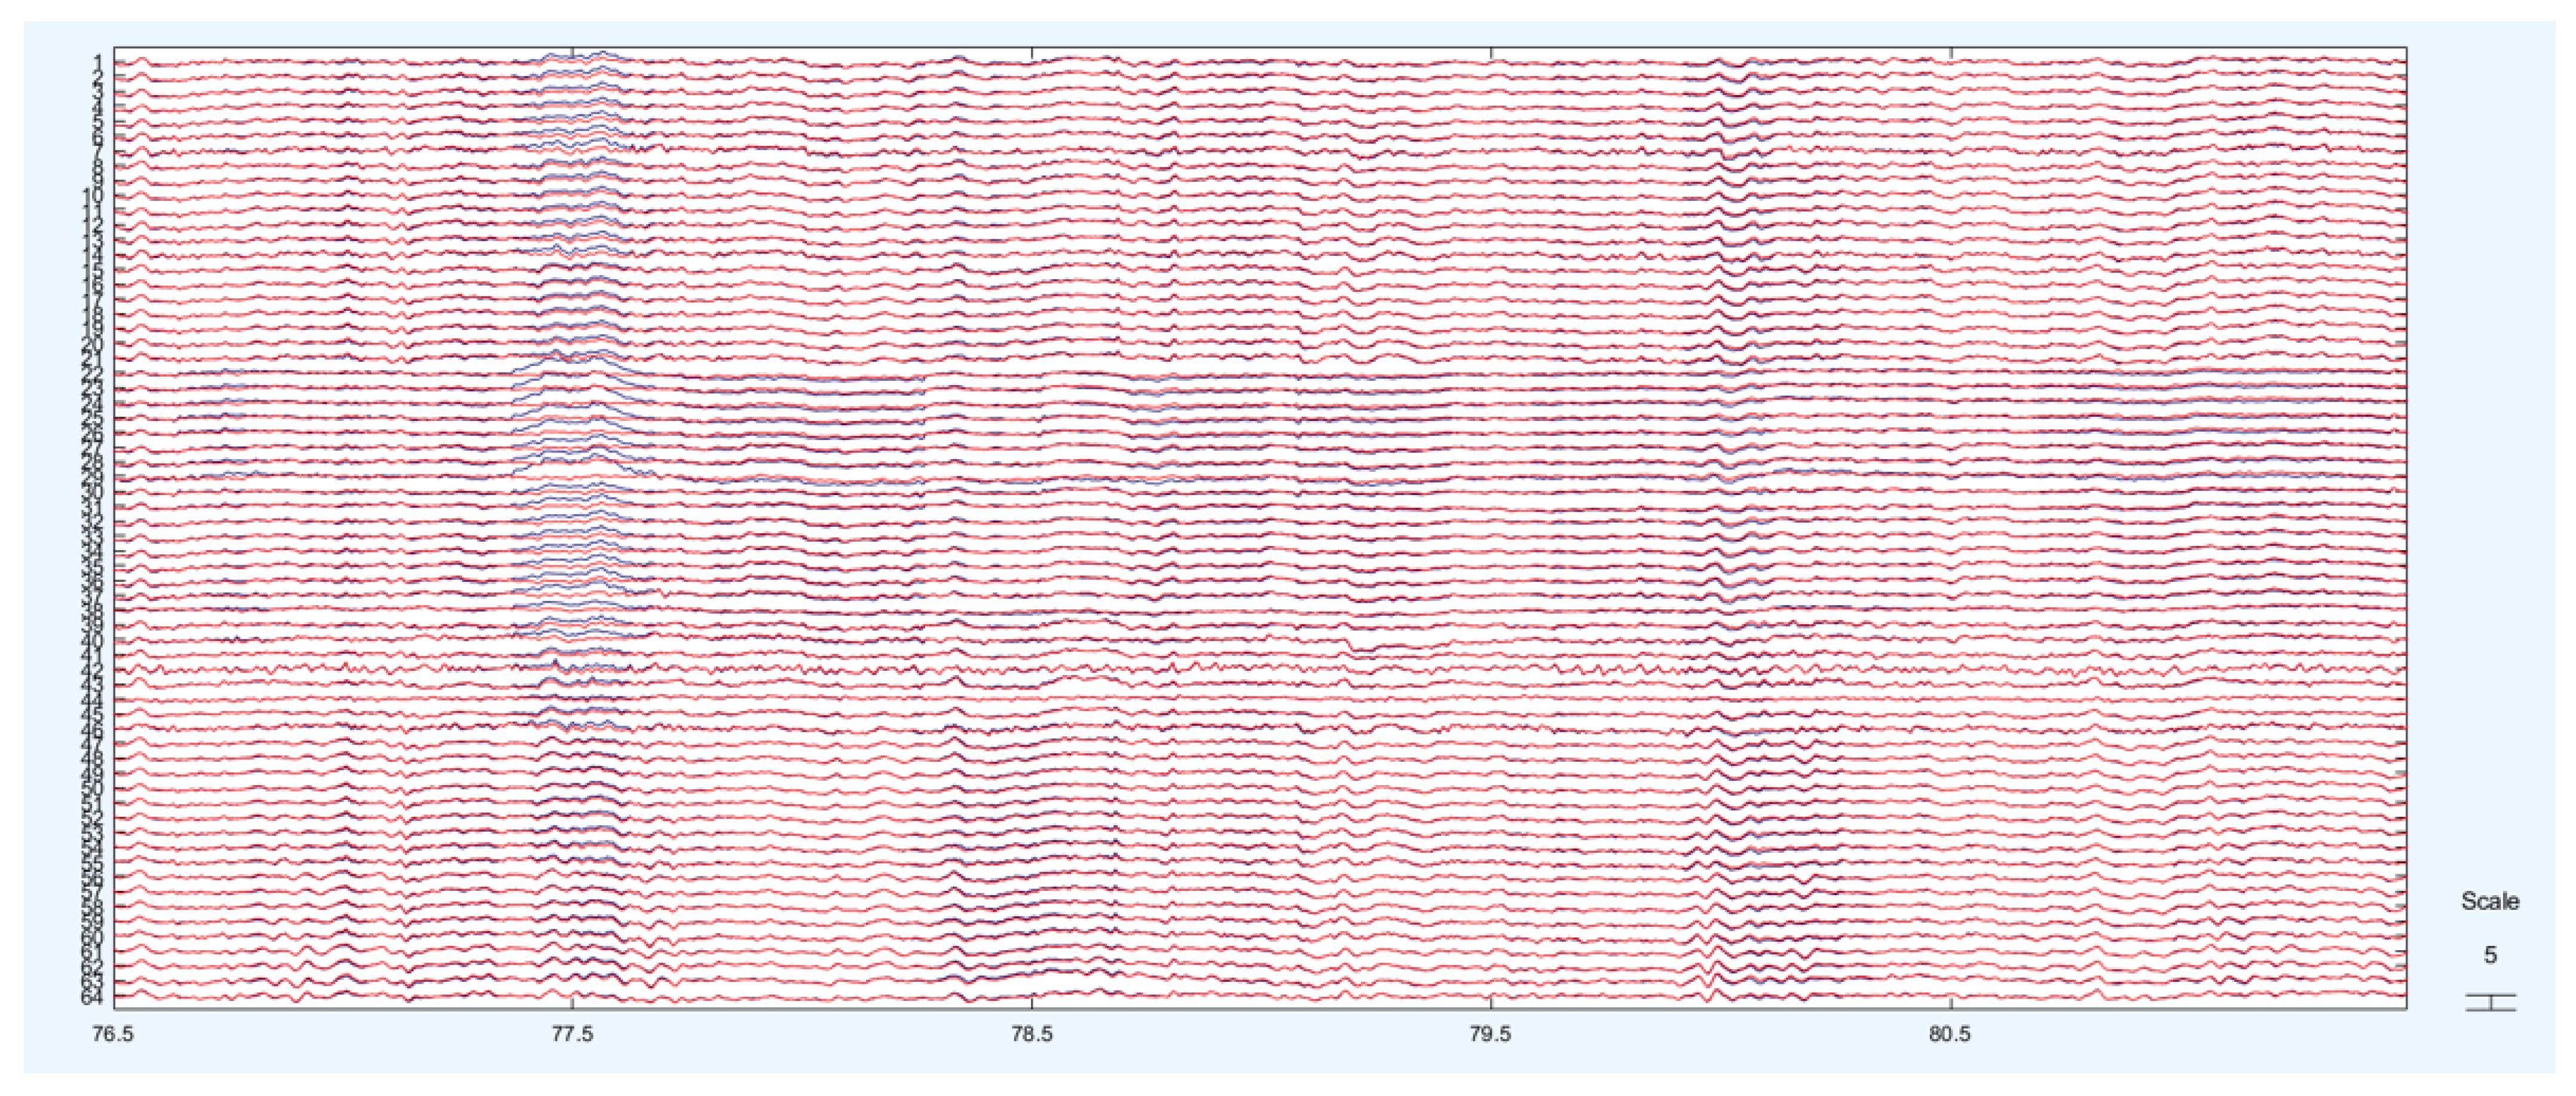

2. Materials and Methods

3. Results

3.2. Spectral and Channel-Based Analysis Results